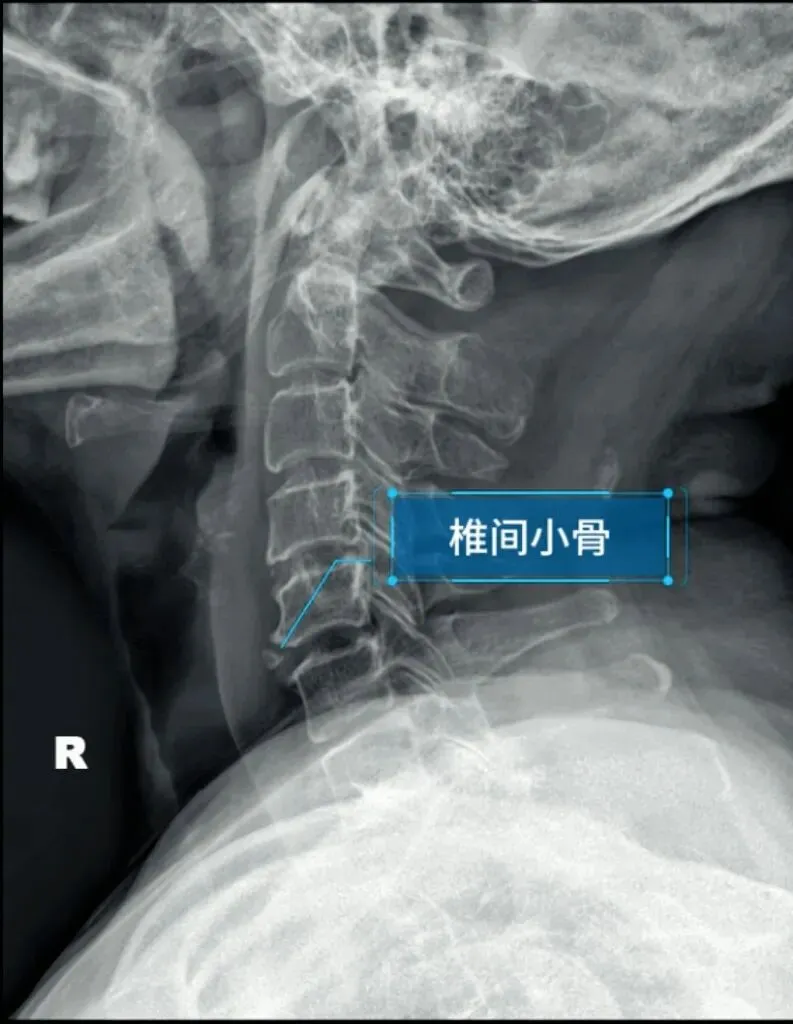

椎间小骨与前纵韧带钙化较难鉴别,所以容易被误认为前纵韧带钙化。